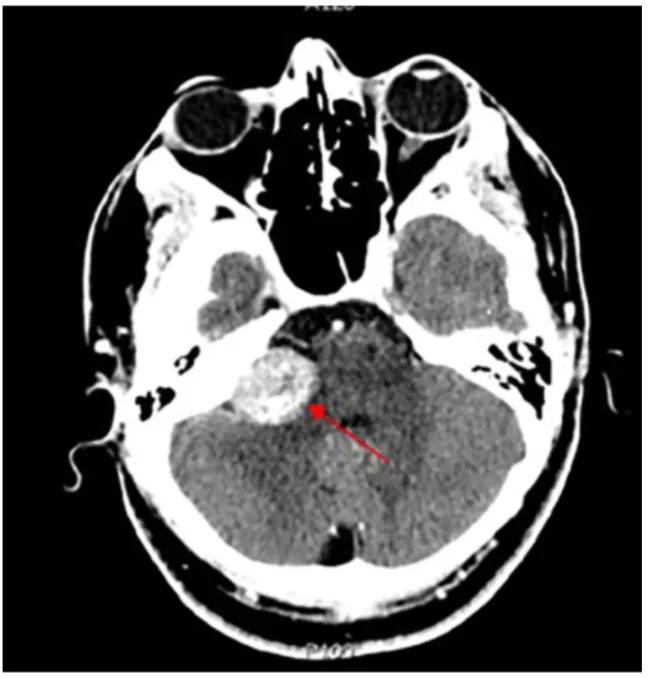

增强CT扫描图像显示,右侧桥小脑角区存在一大小约2.3厘米的边界清晰轴外肿块,该肿块呈现明显强化,并向右侧内听道内延伸,影像学表现符合右侧听神经鞘瘤(图中红色箭头指示)。